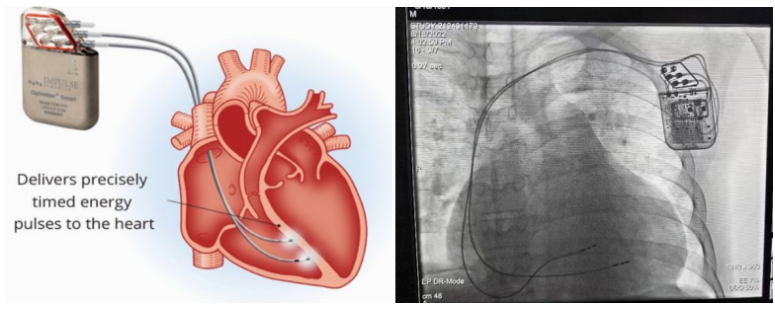

①植入式心臟復(fù)律除顫器

Implantable Cardioverter Defibrillator,ICD

植入式心臟復(fù)律除顫器是一種具有除顫功能的高級起搏器,是一種體積小、能植入患者胸部皮下組織的醫(yī)療設(shè)備。慢性心衰患者易發(fā)生室性心動過速或心室顫動,導(dǎo)致心源性猝死(SCD)。ICD 則能在幾秒內(nèi)自動識別并治療快速室性心律失常,通過低能量心臟轉(zhuǎn)復(fù)和高能量除顫等功能,顯著降低惡性室性心律失常引起的猝死風(fēng)險??杉皶r自動為患者轉(zhuǎn)復(fù)心律,通俗地說就是裝在體內(nèi)的自動除顫儀。